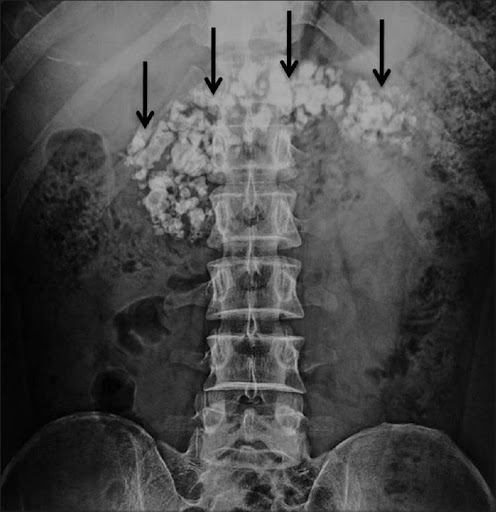

Chronic Pancreatitis

Chronic pancreatitis is a syndrome defined by chronic, progressive pancreatic inflammation, fibrosis, and scarring, resulting in damage to and loss of exocrine (acinar), endocrine (islet cells), and ductal cells. The syndrome is commonly associated with clinical features of abdominal pain, exocrine and endocrine insufficiency, secondary pancreatic cancer, and other complications.